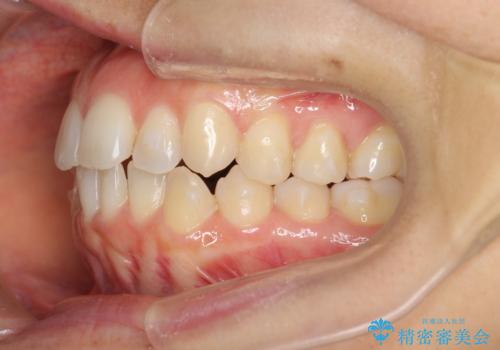

前歯のガタつきをマウスピースで治したい!

- 気になる前歯のガタつきをマウスピースで治療したいと希望され来院されました。

当日に矯正検査を行い、骨格・歯に問題がないことを確認しマウスピースによる矯正治療を進めます。

IPRを前歯部に少量行うことで、非抜歯でも前歯が外に飛び出さない仕上がりを達成できました。